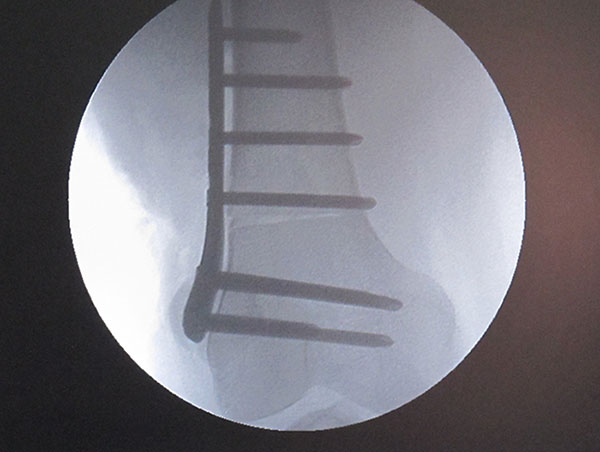

Varising Derotational Distal Femoral Osteotomy